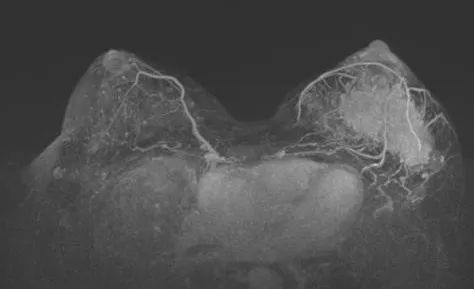

图3. 上图为治疗前,下图为治疗6周期后

治疗6个周期后,乳腺增强MRI显示靶病灶明显缩小,临床疗效评估为PR;腋窝靶病灶消失,临床疗效评估为CR。